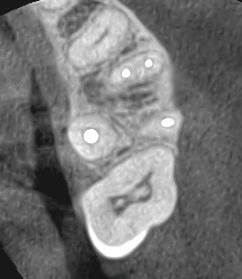

A 25-year-old female student who had recently completed a stressful final exams week noticed a localized, red spot on her palate while brushing her teeth. She reported no pain at first, by the next day the area had become more erythematous and uncomfortable. She presented to Oral Pathology at the University of Oklahoma College of Dentistry as recommended by ENT. She reported the lesion was “fairly painful.” Her dental evaluation was excellent, negative for caries and periodontal disease. She had no recollection of trauma and no signs or symptoms of infection or recent illness. She was healthy with a non-contributory medical history. She was not taking any medications and had no reported illicit drug use.

The clinical photos reveal a quickly progressing, erythematous, slightly swollen nodular area in the midline of the hard palate. The patient had taken a picture on the first day of discomfort and then presented the following day with a slightly larger erythematous area. The central portion of the lesion was even a darker red. (See photos 1 and 2)